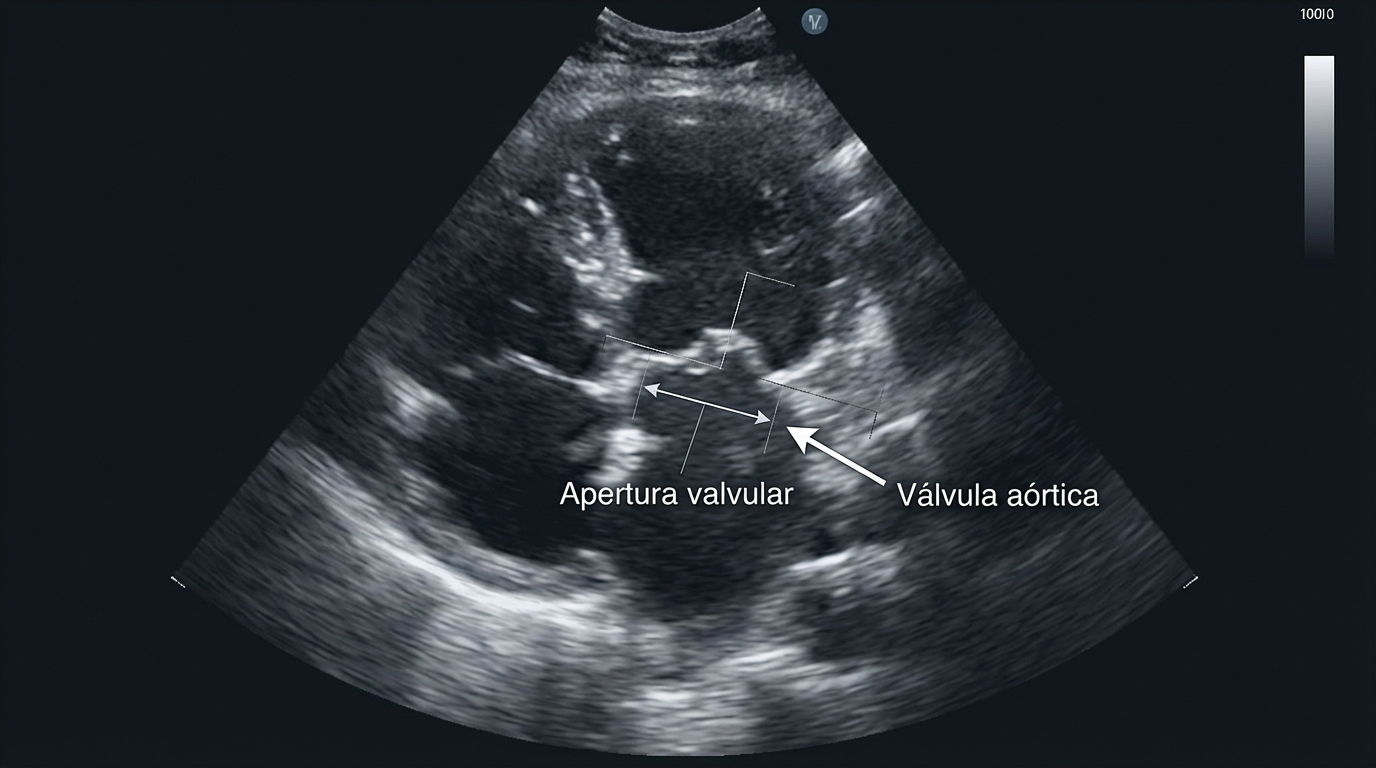

La estenosis aórtica ocurre cuando la válvula aórtica —la puerta por donde la sangre sale del corazón hacia el cuerpo— se estrecha y no se abre por completo.

- Ecocardiograma, que permite medir el grado de estrechamiento valvular